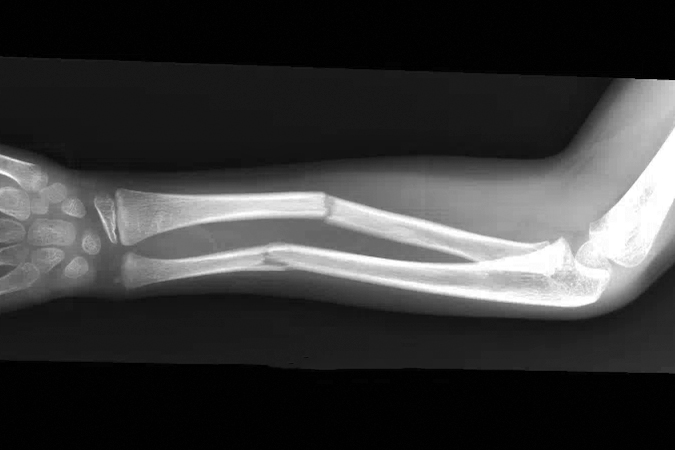

Greenstick fracture

- Pediatric forearm fractures are typically described as either complete or greenstick fractures.4

- Greenstick fractures are incomplete, partial thickness fractures in which only the cortex and periosteum are interrupted on one side of the bone but intact on the other side.4,18

- Greenstick fractures are more common among younger children under the age of 10 years, particularly boys, while completed or short oblique fractures are more common in older children.18,19

- The most common mechanism of injury is a fall on an outstretched hand (FOOSH), but other possible causes include car accidents, bike accidents, sports injuries, and non-accidental trauma.18

Imaging

- Radiology studies - X-ray